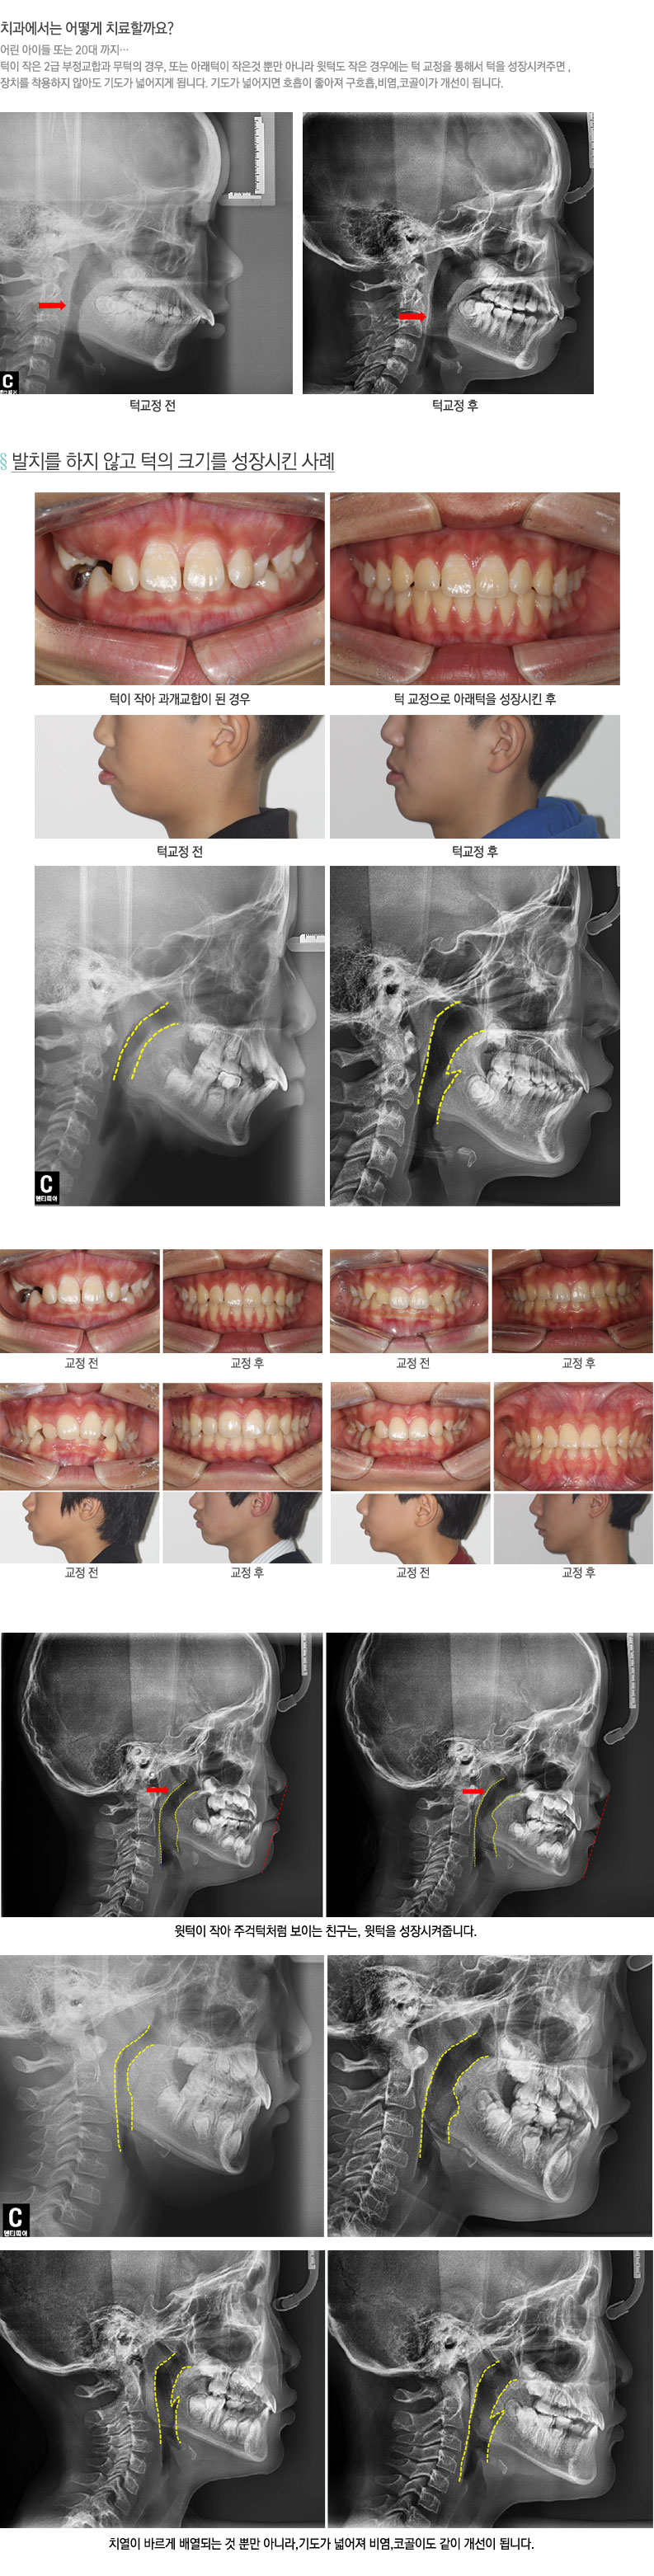

HOME > Ä¡¾Æ±³Á¤Å¬¸®´Ð > ¾î¸°ÀÌ ºñ¿°,ÄÚ°ñÀÌÄ¡·á